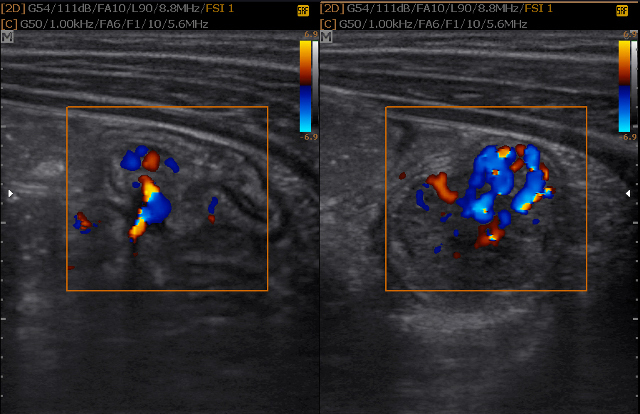

In besonderen Fällen werden die Bauchgefäße, Lymphknoten, die Darmdurchblutung, der Schluckakt der Speiseröhre oder auch die Schilddrüse untersucht.